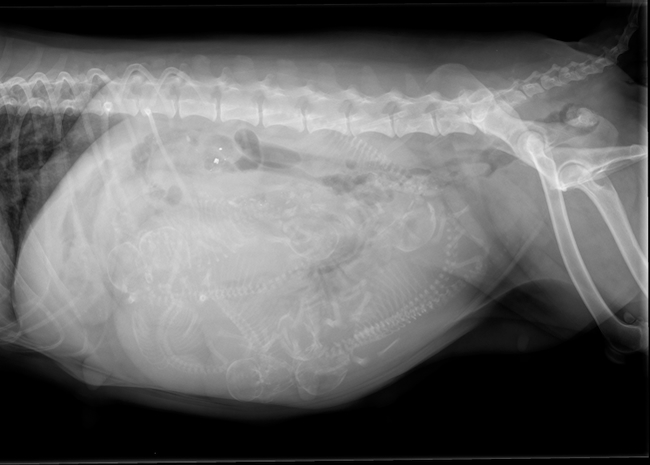

Op woensdag 2 december 2025 is Charly bevallen van 7 prachtig pups en mooie kleuren.